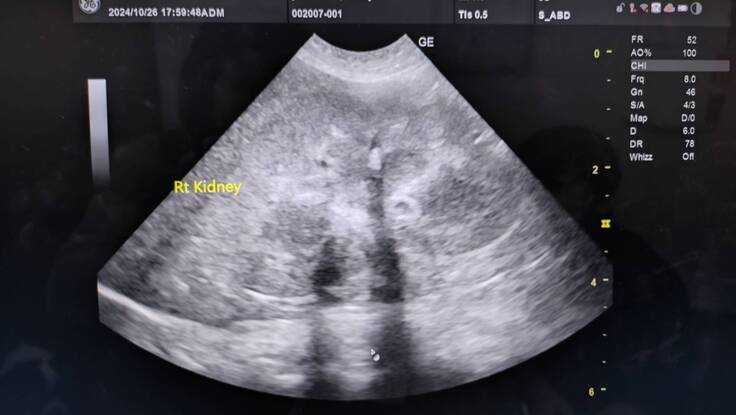

エコー写真→キラキラ白く写っているのが菌、脂肪や結石様のもの浮遊物

腎臓結石あり→悪さはしていない

右、左の腎臓も変形などなし

今のところ腫瘍とかは確認できるものはなさそう